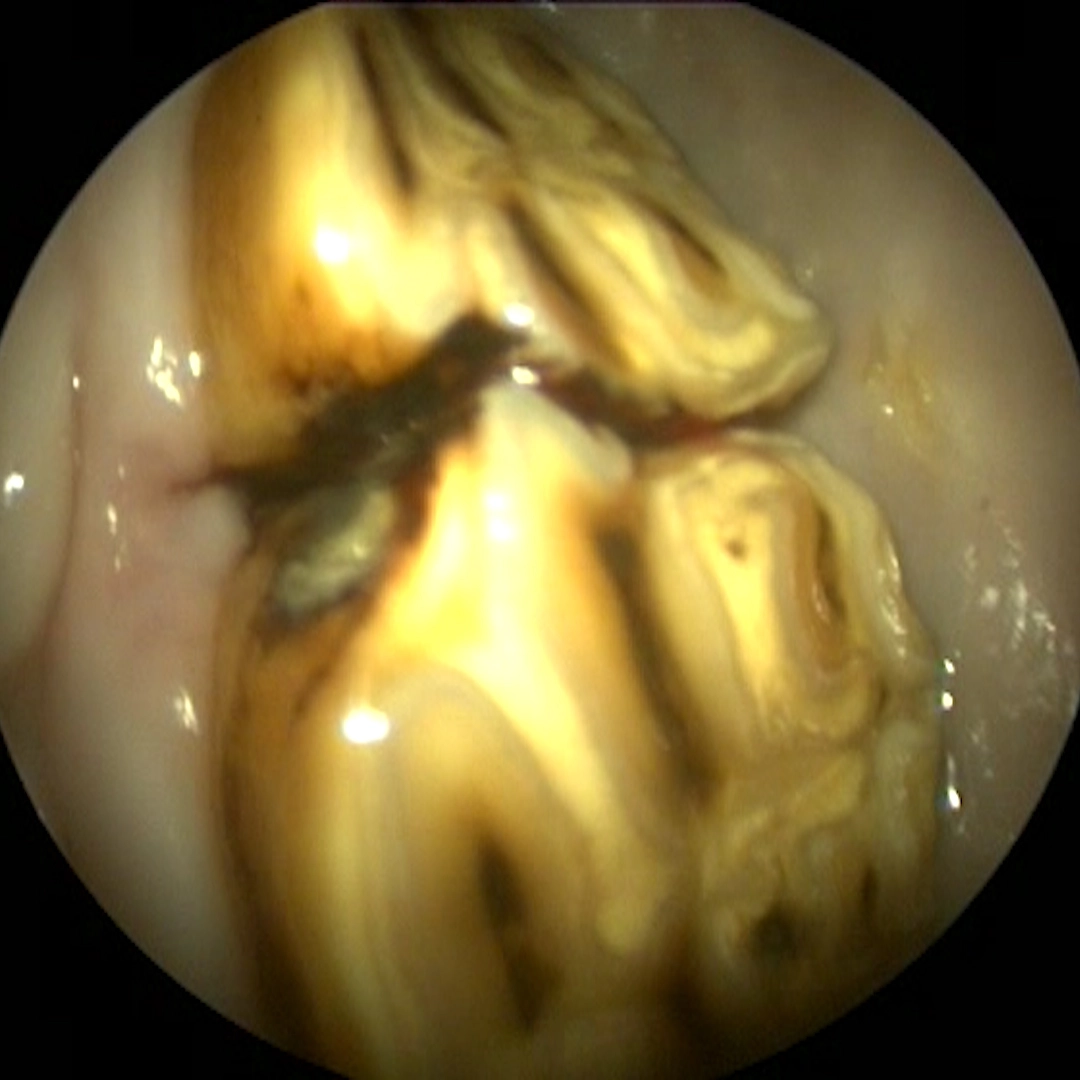

Abnormal spaces between teeth allow feed material to become trapped and compressed into the gum tissue.

Over time, this leads to inflammation, infection, and damage to supporting structures if not addressed.

Therapy may involve cleaning the affected area, reshaping tooth surfaces, or corrective dental techniques to reduce food accumulation.